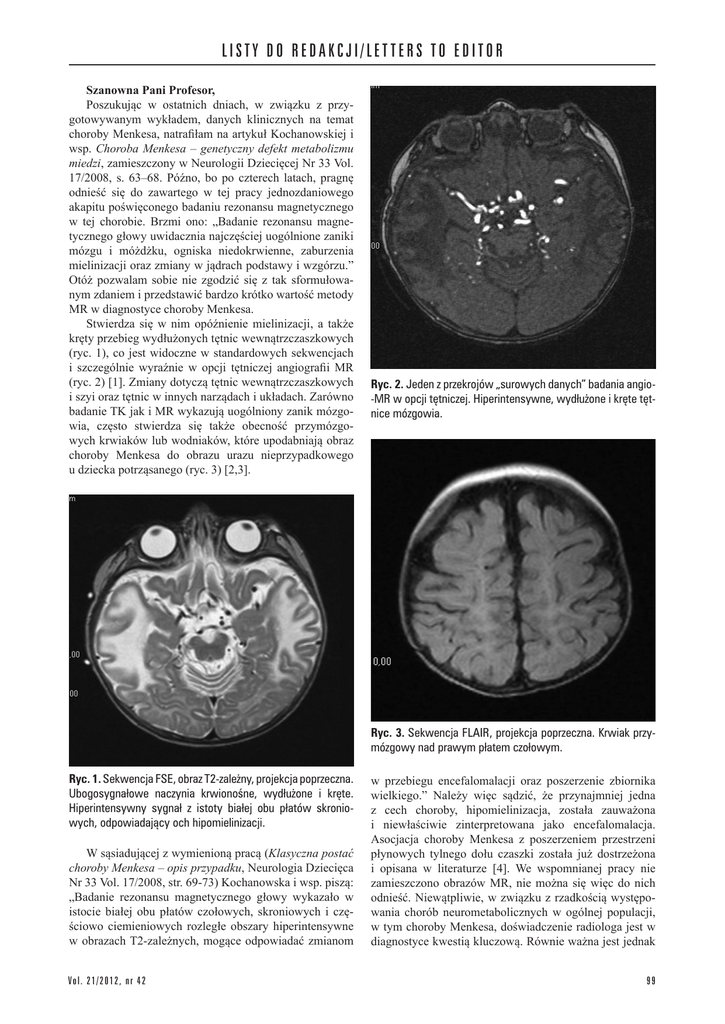

Ryc. 3. Sekwencja FLAIR, projekcja poprzeczna. Krwiak przymózgowy nad prawym płatem czołowym.

badanie TK jak i MR wykazują uogólniony zanik mózgowia, często stwierdza się także obecność przymózgowych krwiaków lub wodniaków, które upodabniają obraz

choroby Menkesa do obrazu urazu nieprzypadkowego

u dziecka potrząsanego (ryc. 3) [2,3].